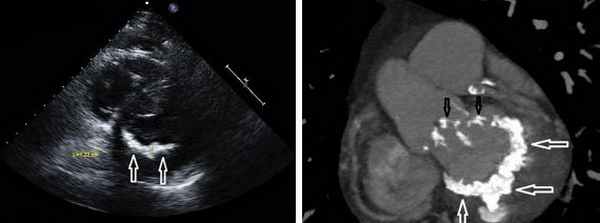

- Инфекционный эндокардит (перфорация или разрушение створки (рис. 7).)

![]() | Рис. 7 Препарат митрального клапана, иссеченный во время операции. Створки разрушены с формированием митральной недостаточности, видны массивные вегетации. |

В диагностике недостаточности митрального клапана существенную роль играет эхокардиография. Применение трансторакального и чреспищеводного сканирований позволяет определить характер патологических изменений на клапане (инфекционный эндокардит, миксоматозная дегенерация и т.д.), оценить выраженность нарушений внутрисердечной гемодинамики (определить степень регургитации, ее характер). Данные эхокардиографической картины вместе с клиническими проявления и позволяют сформулировать показания к хирургическому лечению.

Другой важный инструментальный метод диагностики — эхокардиография (Эхо-КГ) . Эхо-КГ — это безболезненное ультразвуковое исследование, которое позволяет исследовать работу сердца в реальном времени. Эхокардиография покажет уменьшение эластичности клапана, его повреждение, размер отверстия митрального клапана и расстояние между его створками. Также при исследовании можно увидеть разрыв папиллярной мышцы и провисание клапанных створок в полость левого предсердия [4] [8] [9] .

Эхокардиография (ЭХОКГ) занимает ведущее место в диагностике недостаточности митрального клапана и определения показаний по тактике ведения больного. При недостаточной информативности трансторакальной ЭХОКГ и уточнения возможности реконструктивной операции на митральном клапане должна быть выполнена чрезпищеводная ЭХОКГ.

ЭХОКГ позволяет определить этиологию митральной недостаточности, ее тяжесть –компенсаторные возможности левого желудочка, наличие осложнений (левожелудочковая недостаточность, легочная гипертензия, правожелудочковая недостаточность), выявить другие пороки сердца.